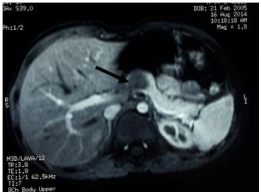

A 9 y/o male, with history of appendectomy and peritonitis, Meckel diverticulum´s surgery 6 years ago and chronic constipation came to the hospital complaining of 1 year of mild to moderate colic epigastric intermittent pain. Two months before admission he had abdominal distension, intermittent vomits and sporadic headache. His primary care physician ordered an abdominal US which showed a 2.5x1.9 cm hypoechogenic ovoid lesion; later, the SSCT and Magnetic resonance imaging (MRI) revealed a 2.1x1.6x1.8cm tumor on the pancreas body (Figure 3). Tumor markers CA 19-9 (Normal: < 37U/mL) and AFP were normal. An Endoscopic Ultrasound (EUS) biopsy showed only adipose tissue. A distal pancreatectomy of the neck, body and tail was performed. AP revealed a 1.7x1.4x1.2 cm tumor lesion on the tail of the pancreas. Microscopy showed solid and pseudopapillary patterns on tumor cells (Figure 4). On IHC tumor cells were positive for cycline D1 (Figure 4), progesterone receptors, Ki-67 < 2% and negative for pan cytokeratin, CD-99, estrogen receptors, chromogranin, synaptophysin and not representative vimentin. The patient was discharged at 10 days post-surgery.

Figure 4 Contrast MRI of the upper abdomen. Arrow shows the tumor.